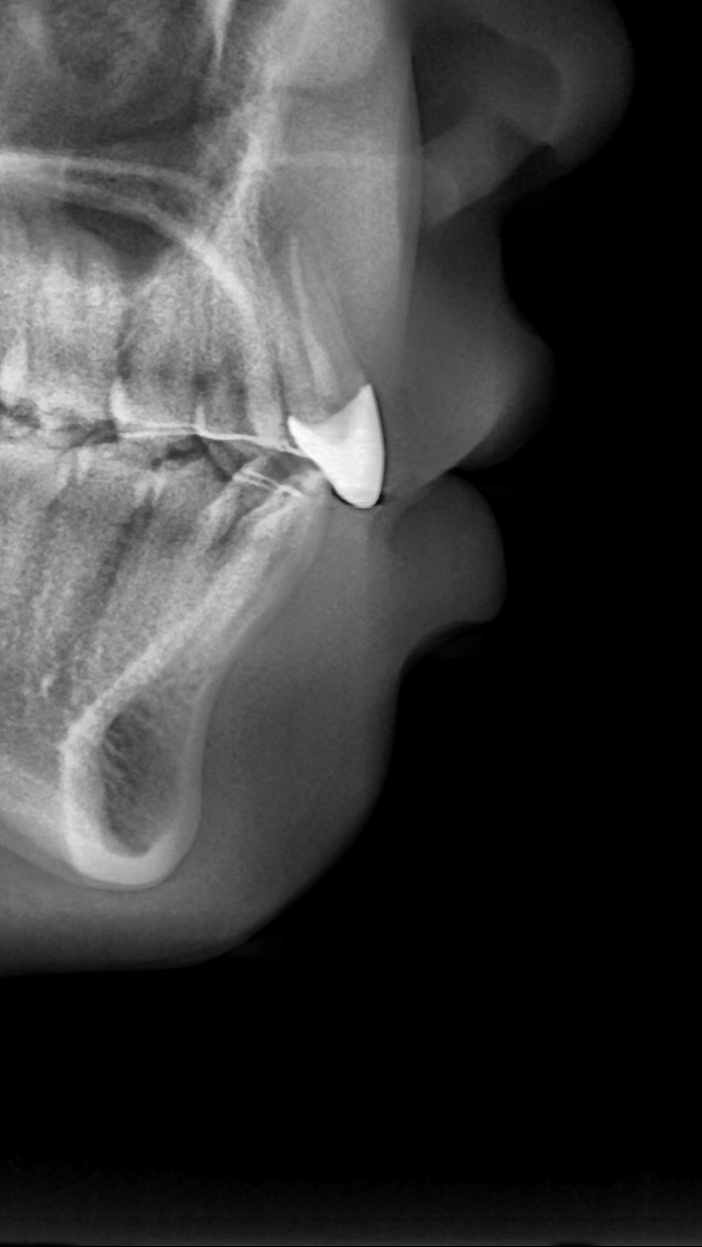

아래쪽 두 번째 어금니(제2대구치)가 선천적으로 없는 결손치로서, 사랑니(제3대구치)가 있으나 앞으로 쓰러져서 잘 안 씹히고 썩어 있습니다.

이런 경우 사랑니를 발치하고 임플란트를 하는 방법도 있으나, 본인 치아를 살리고 싶어하셔서 교정으로 접근하였습니다.

부분교정을 통해 누워있던 사랑니를 세웠으나, 씹는 면에 충치가 있습니다.

교정종료 후 보철치료(인레이)를 통해 씹는 기능을 회복시켰습니다.

누워있던 이가 세워져서 음식물이 더 잘 씹히게 되었습니다.

또한 음식물이 끼지 않게 되어 구강위생관리도 원활하게 되었습니다.